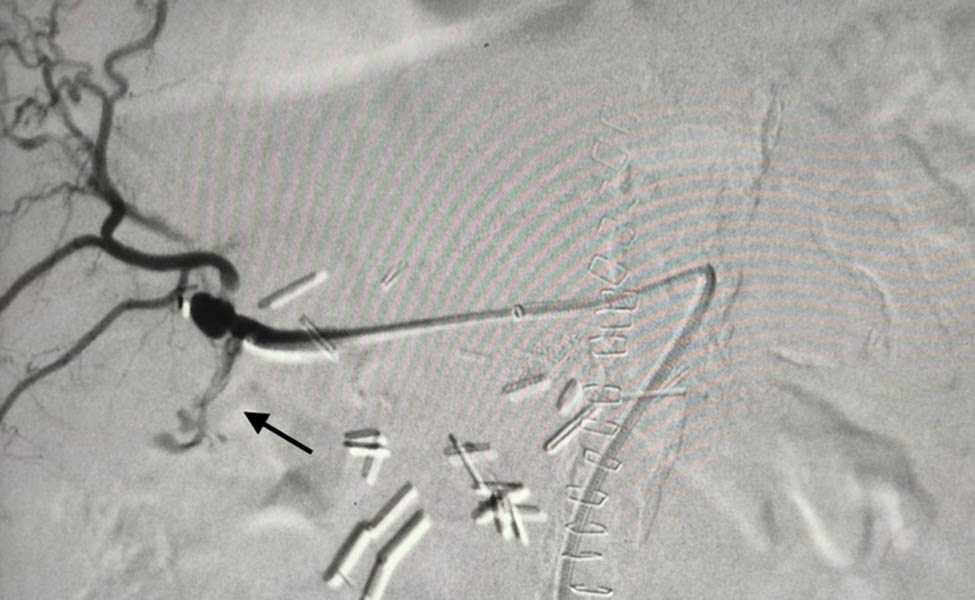

An endovascular approach was deemed the optimal strategy. The SMA was cannulated with the use of a “Simmons” catheter under local anesthesia and direct puncture of the common femoral artery. A 6Fr-45cm sheath was advanced, and an angiogram revealed the aberrant right hepatic artery, as well as the pseudoaneurysm at the bifurcation of the hepatic artery (Figure 3). The original 0.035-in. stiff wire was replaced with a 0.035-in. “Rosen” wire, and a 5Fr “Vertebral” catheter was advanced distally beyond the pseudoaneurysm. In order to seal the pseudoaneurysm and the right hepatic artery, six detachable coils were deployed (Interlock-18 Fibered IDC occlusion system, Boston Scientific, Marlborough USA) of various sizes (8 × 100 n = 2, 6 × 100 n = 1, 4 × 100 n = 2, 4 × 60 n = 1). Stent graft deployment was not considered, since the location of the pseudoaneurysm at the bifurcation of the aberrant hepatic artery did not provide an adequate landing zone and diameter mismatch between the hepatic artery and its branches. Final angiography demonstrated successful occlusion of the pseudoaneurysm, without compromise of liver blood supply from the coeliac artery (Figure 4).

Intra-op angiography. The arrow shows the contrast extravagation.

Final angiography with coils in place. No hemorrhage identified. Arrow indicates the previous site of extravagation.